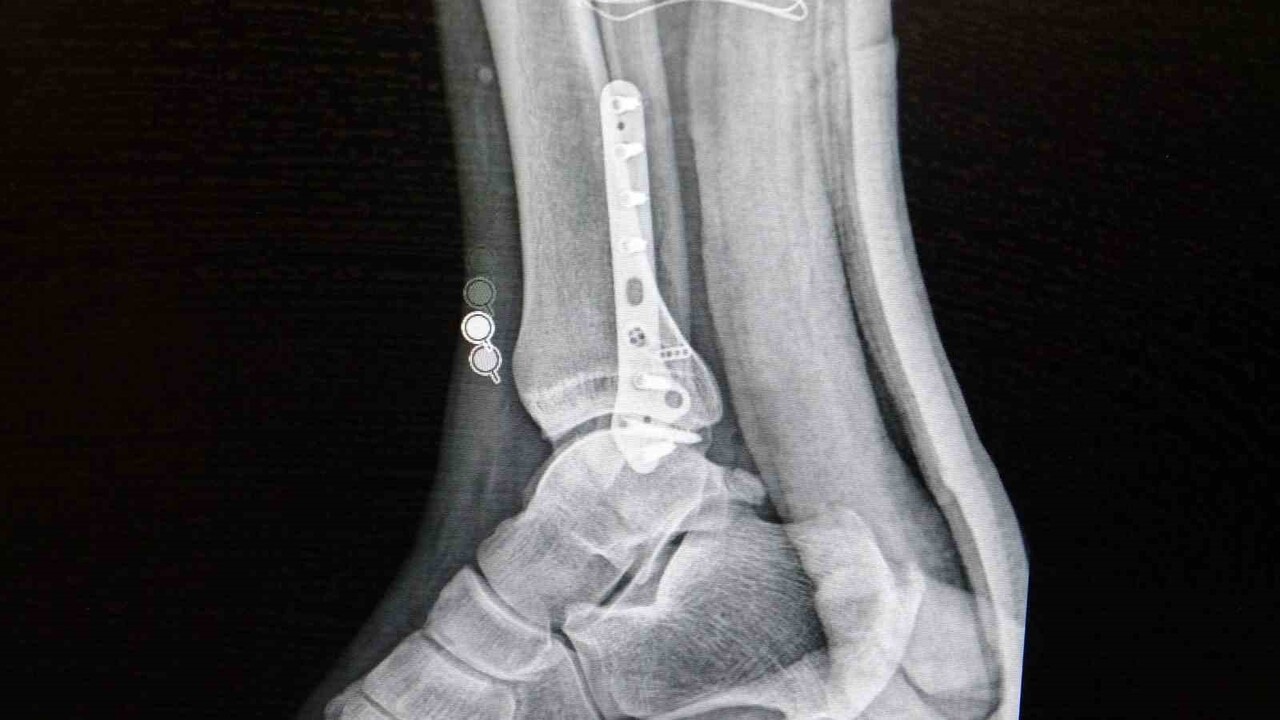

Ortopedi polikliniklerine en çok ayak bileği, diz ve omuz yaralanmalarıyla başvurulduğunu aktaran Demirbaş, futbolda görülen yaralanma oranlarının öne çıktığını belirtti. Menisküs yırtıkları, ön çapraz bağ yırtıkları, iç ve dış yan bağ yaralanmaları, aşil tendon kopmaları, ayak bileği bağ yaralanmaları ve spora bağlı kırıkların sık görüldüğünü söyledi.